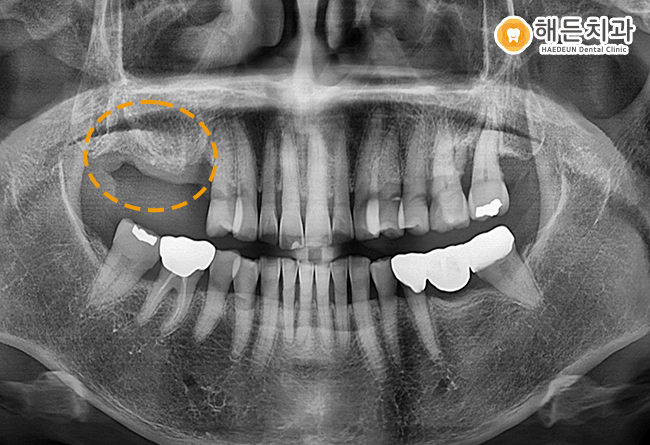

위 환자분께서는 오른쪽 위의 어금니가 상실되어 본원을 찾아주셨습니다.

현재 오른쪽 위의 어금니가 상실되었기에, 왼쪽 어금니로 거의 식사를 하고 계신 상황이었는데요.

이렇게 한쪽으로만 식사하시는 편측 저작을 하게 되면,

힘이 한쪽 치아에만 집중이 되어 왼쪽 치아에 무리가 갈 수 있습니다.

또한 치아 뿐만 아니라 턱관절에도 악영향을 줄 수 있으며

상실된 치아 주변의 치아들의 이동하여

치아 배열이 흐트러지는 등의 문제를 야기할 수 있기에, 빠른 치료가 필요하였습니다.